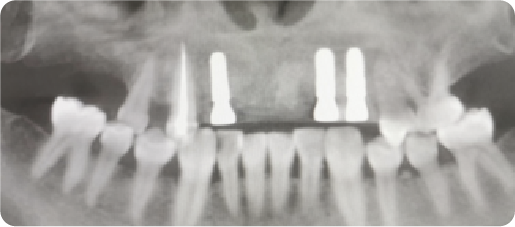

Multi-unit Dental Implant Case

BEFORE

VS

AFTER

Name:MS DengAge:31

Evaluation: Long-term use of a removable denture has led to compromised mastication and severe alveolar bone resorption.

Treatment Plan:The solution involves three dental implants that anchor a five-tooth bridge.Two artificial teeth are suspended between the implant-supported crowns, restoring all five missing teeth.

Patient Feedback:Tought&Feel like natural teeth.Unlike removable dentures, implant-supported teeth are designed for lasting comfort, security, and a natural appearance—without slipping or the need to grind down adjacent teeth.